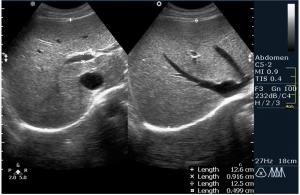

По всей видимости пузырь увеличен, напряжен, содержимое 2 крупных конкремента,один из которых вклинен.

Доктор Марио! Фиксированный камень шейки желчного пузыря. Еще один камень в просвете. Не знаю, употребляете ли Вы такой термин, но я бы еще сказал "водянка желчного пузыря". Показание к оперативному лечению желче-каменной болезни. Симптома "трехслойности стенки" не увидим. Пузырь перерастянут. Кстати, в последнее время встречается все большее и большее количество случаев желче-каменной болезни у пациентов молодого возраста. От 18 лет.

Вы совершенно правы, это холецистолитиаз с вклинённым камнем шейки (impacted GB neck stone) с перерастяжением пузыря, или водянка (GB Hydrops). Сегодня была успешнo оперирована.